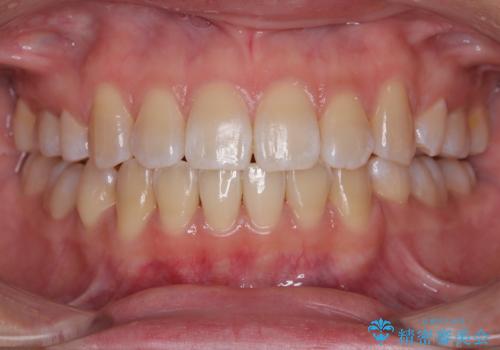

[ マウスピース矯正治療 ] がたつき ねじれのある前歯をきれいにしたい

![[ マウスピース矯正治療 ] がたつき ねじれのある前歯をきれいにしたいの症例 治療後](https://seimitsushinbi.jp/wp/wp-content/uploads/2025/04/IMG_0097-500x350.jpg?v=1745225947)